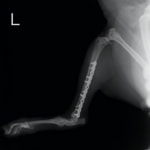

トイプードル 右遠位橈尺骨短斜骨折のALPSによる内固定

当院ではAdvanced Locking plate system(ALPS)と、Locking compression plate system(LCPS)という骨接合法で骨折症例の治療を行っています。

Advanced Locking Plate System

従来型のプレートのように広い面積で骨と接するプレートを用いて固定を行った場合、プレート下の骨はプレートとの接触面において血行が絶たれ壊死し、それがリモデリングされると骨密度が低下する。この骨密度の低下防ぐために、骨折部局所への血行を温存することの重要性が近年改めて認識されるようになってきている。Advaed Locking Plate System (ALPS)は従来型のプレートシステムの欠点を改良し、より使いやすく、より骨への血行を阻害しないようにというコンセプトで作られた。